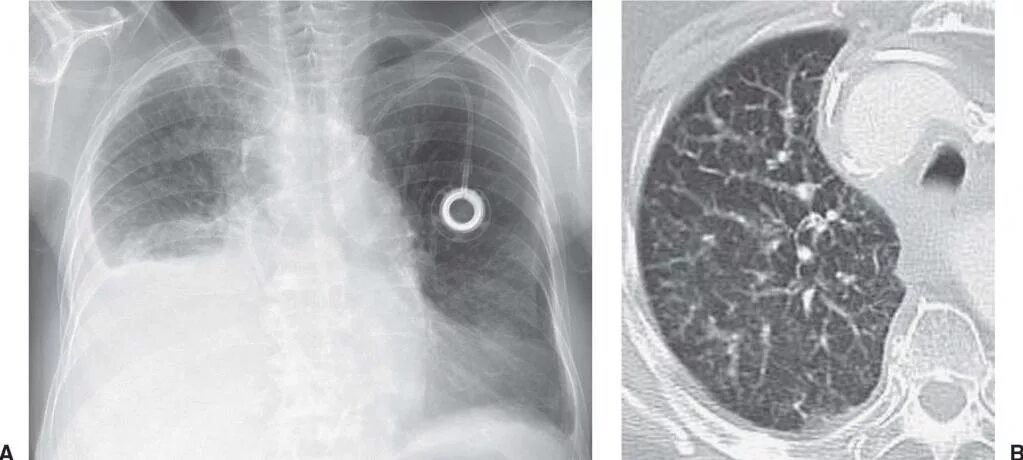

Метастазы в легких терапия